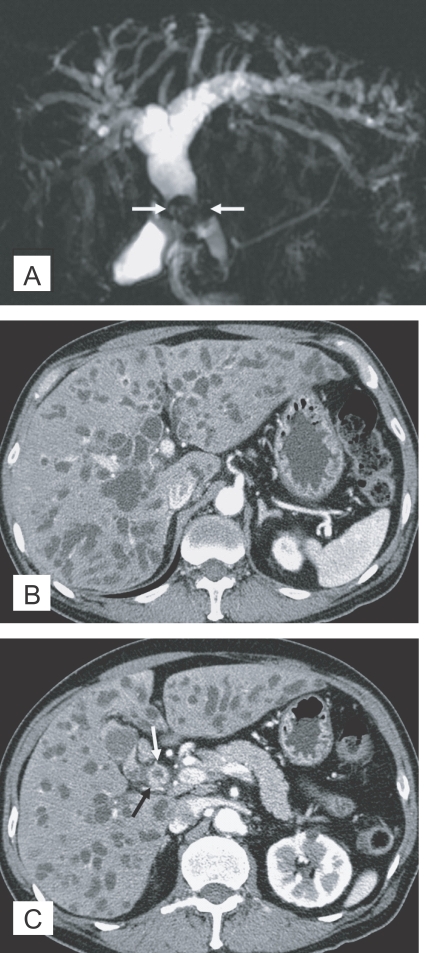

The CT finding of clonorchiasis is diffuse dilatation of the peripheral intrahepatic bile ducts, without dilation of the larger bile ducts or extrahepatic ducts (Fig. 3A). This finding is known to be the pathognomonic findings of clonorchiasis (Lim, 1990), however, it is also observed in cured infection.

In contrast to sonography showing an increased echogenicity of the ductal wall, CT failed to show thickening of the bile duct wall (Choi et al., 1989). A recent experimental study, however, suggested that an active infection could be differentiated from cured clonorchiasis by using the periductal enhancement with the thickened bile duct walls on dynamic contrast-enhanced CT (Lee et al., 2003). The contrast-enhanced CT visualized a characteristic finding, transient hepatic attenuation differences (THAD). The finding was interpreted as an outcome of new vascularization in the thickened bile duct wall, which disappeared after cure of clonorchiasis (Fig. 3B). They also asserted that some adult worms were demonstrated on their thin-section CT scans (Lee et al., 2003).

MR imaging has been used in diagnosis of various diseases of the biliary system, and MR cholangiography is a relatively new non-invasive imaging modality for evaluation of the biliary pathology. MR imaging can show the characteristic findings of clonorchiasis with diffuse, mild dilation of the small intrahepatic bile ducts, particularly in the periphery of the liver (Choi et al., 1998). According to a recent study, MR cholangiography also found "too many intrahepatic ducts" sign in 62% (16 of 26) of patients with clonorchiasis (Jeong et al., 2004). Periductal enhancement was more frequently seen on MR imaging, compared to CT, due to a higher spatial resolution of the soft tissue (Fig. 4). The filling defects representing worms were elliptical, irregular shaped, and hypointense lesions on the T2-weighted images and MR cholangiography.

Fig. 3

Contrast-enhanced CT findings of the liver in clonorchiasis patients. A. A 52-year-old man, who underwent liver transplantation in China 1 month before CT examination, shows diffuse and mild dilatation of the peripheral intrahepatic bile ducts (arrows). The transplanted liver had been infected with C. sinensis. B. Periductal enhancement (arrows) with the thickened bile duct walls on hepatic arterial phase of dynamic study, which possibly represents active infection, in a 61-year-old man.

Fig. 4

MR findings of the liver in clonorchiasis patients. A. MR cholangiography in a 58-year-old man, who underwent cholecystectomy 10 year ago, showing diffuse and uniform dilatation of the peripheral intrahepatic bile ducts. B. Periductal enhancement of mildly dilated intrahepatic bile ducts (arrows) on hepatic arterial phase of dynamic study of gadolinium-enhanced echo fast gradient echo 3D (TR/TE, 7/2) transverse image, which possibly represents active infection, in a 60-year-old man (Courtesy of Dr. Yong Yeon Jeong, Gwangju, Korea).

Fig. 3 Contrast-enhanced CT findings of the liver in clonorchiasis patients. A. A 52-year-old man, who underwent liver transplantation in China 1 month before CT examination, shows diffuse and mild dilatation of the peripheral intrahepatic bile ducts (arrows). The transplanted liver had been infected with C. sinensis. B. Periductal enhancement (arrows) with the thickened bile duct walls on hepatic arterial phase of dynamic study, which possibly represents active infection, in a 61-year-old man.

Fig. 4 MR findings of the liver in clonorchiasis patients. A. MR cholangiography in a 58-year-old man, who underwent cholecystectomy 10 year ago, showing diffuse and uniform dilatation of the peripheral intrahepatic bile ducts. B. Periductal enhancement of mildly dilated intrahepatic bile ducts (arrows) on hepatic arterial phase of dynamic study of gadolinium-enhanced echo fast gradient echo 3D (TR/TE, 7/2) transverse image, which possibly represents active infection, in a 60-year-old man (Courtesy of Dr. Yong Yeon Jeong, Gwangju, Korea).